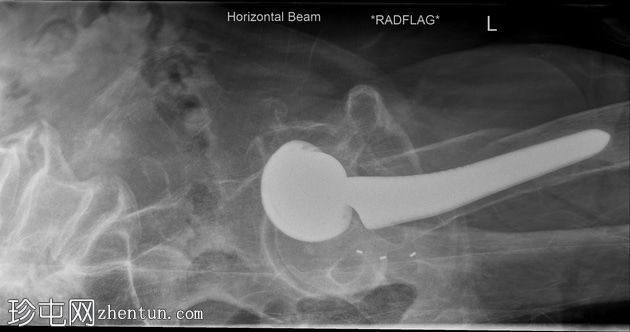

X光片

正面

侧面

可见左髋关节假体。左侧股骨近端存在轻微移位的假体周围骨折。

初次X光片和后续CT扫描均可见左股骨假体周围骨折。温哥华分类系统是目前最广泛使用的髋关节假体周围骨折分类系统。本例患者为温哥华B2型骨折。

患者随后接受了手术固定和翻修关节置换术。